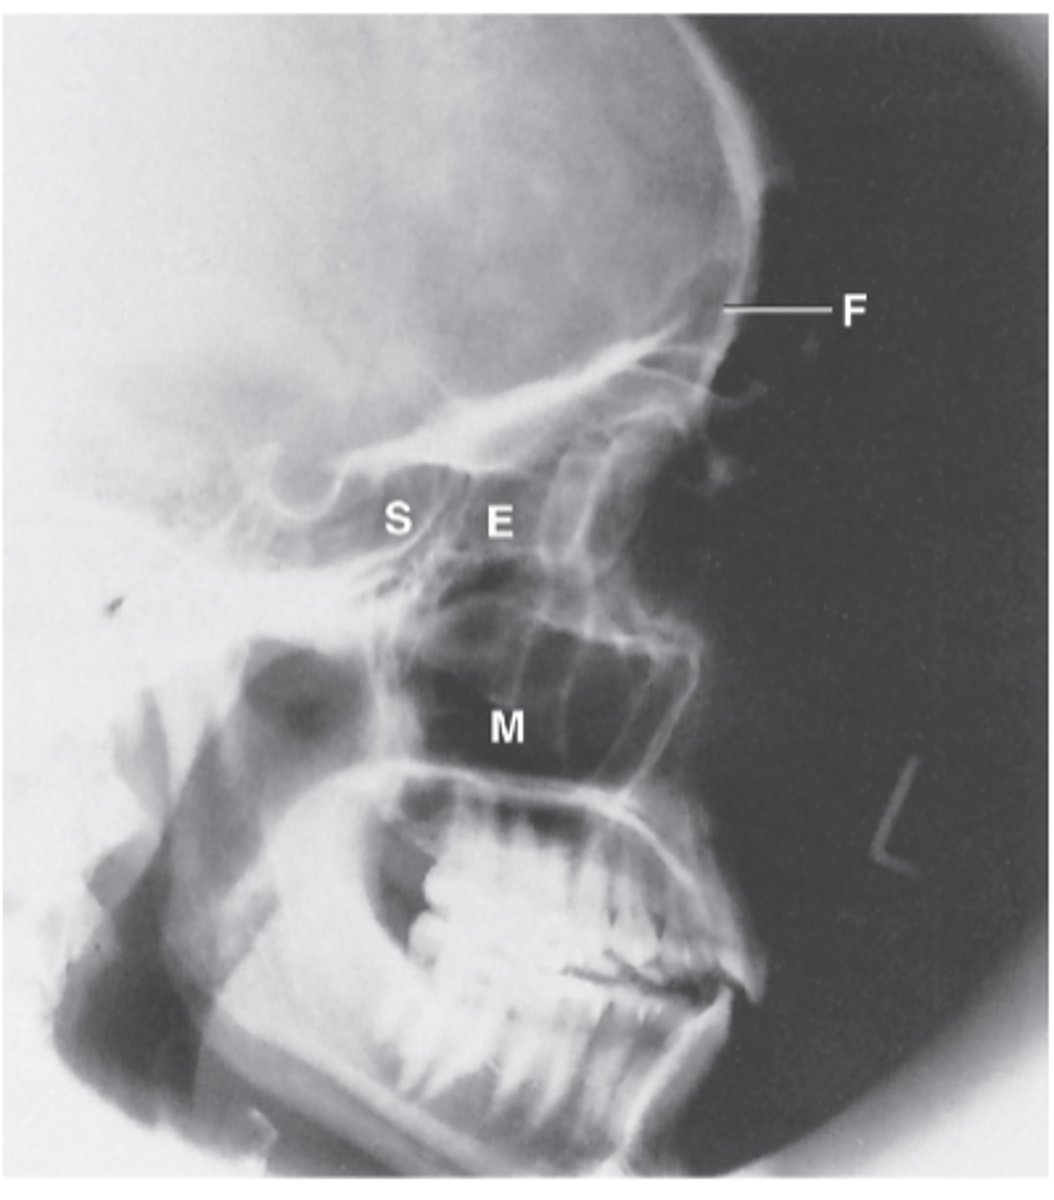

Ethmoid Sinus

E

Sphenoid Sinus

S

Maxillary Sinus

M

Frontal Sinus

F

Lateral Sinuses

What projection is this?

Midway between the EAM and the outer canthus

What is the CR for Lateral Sinuses?

Ethmoid

Sphenoid

Frontal

Maxillary

What sinuses are demonstrated on a Lateral sinuses radiograph?

Interpupillary line (IPL)

What line should be perpendicular to the IR for Lateral Sinuses?

Midsagittal plane (MSP)

Orbitomeatal line (OML)

What lines should be parallel to the IR for Lateral Sinuses ?